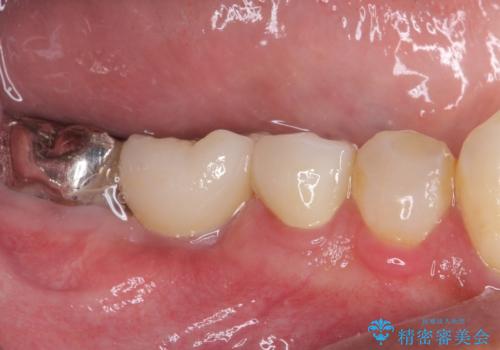

折れてしまった奥歯 インプラントによる補綴治療

診査の結果、5本の奥歯を抜歯してインプラントによる補綴治療が必要と診断されました。

患者様が違和感を感じていない左下の奥歯の治療は今回は見送り、それ以外の治療が必要な奥歯を治療することとしました。

左上に仮歯が装着されたからは咬み合わせが安定し、スムーズに治療を進めることができました。